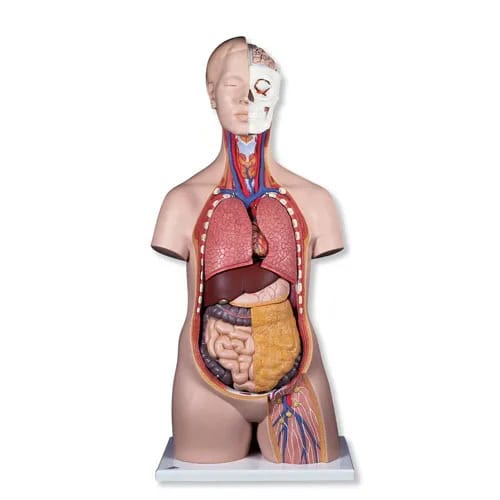

1000200

Torso tweeslachtig met open rug 28-delig